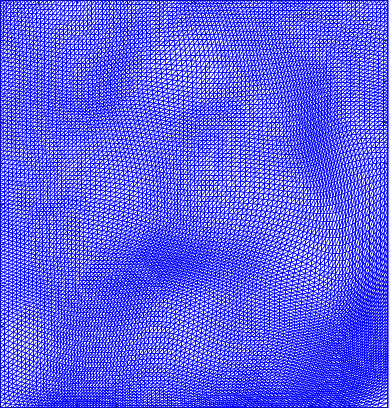

Figure 5 shows the ground truth and recovered maps of the registration maps in the last row of Table 4. It can be seen that ground truth low-rank mapping shown in Figure 5(a) resembles the recovered low-rank mapping shown in Figure 5(c). This again shows that we could obtain a meaningful mapping from the decomposition.

Figure 6 displays the 4 mappings as in Example 3 and 4. Again, we can see that after the decomposition of the Beltrami descriptor, the decpmposed mappings to large extent resemble the corresponding ones.